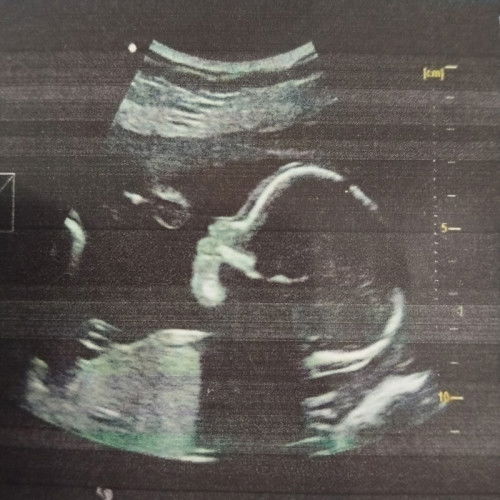

my natamaan ba ang tiyan mo? ako last time nadapa pero tuhod ko lang nagasgasan pero di natamaan ang tiyan ko..nagpacheck agad ako sa ob ko kinabukasan, sa ultrasound clear results, no sign of bleeding .. mas mabuti pa check agad sa ob baka may bleeding sa loob if natama ang tiyan o likod sa hagdan